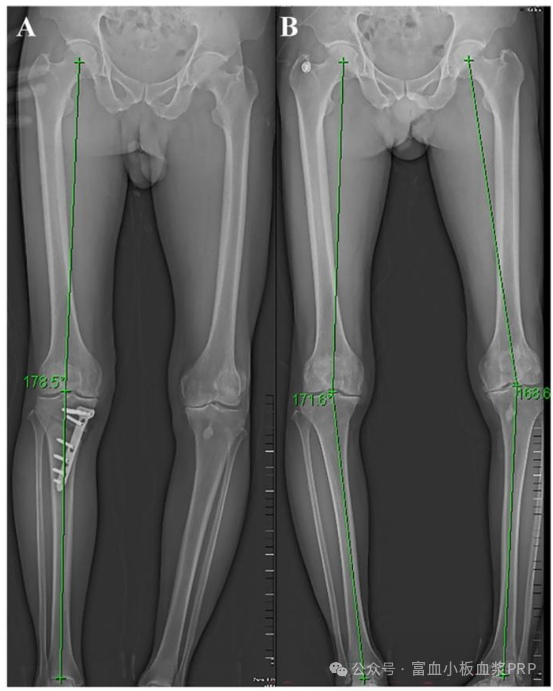

術前評估:醫(yī)生會通過 X 光、MRI 檢查膝蓋力線、軟骨磨損程度,再結合年齡、體重等,判斷是否適合手術;